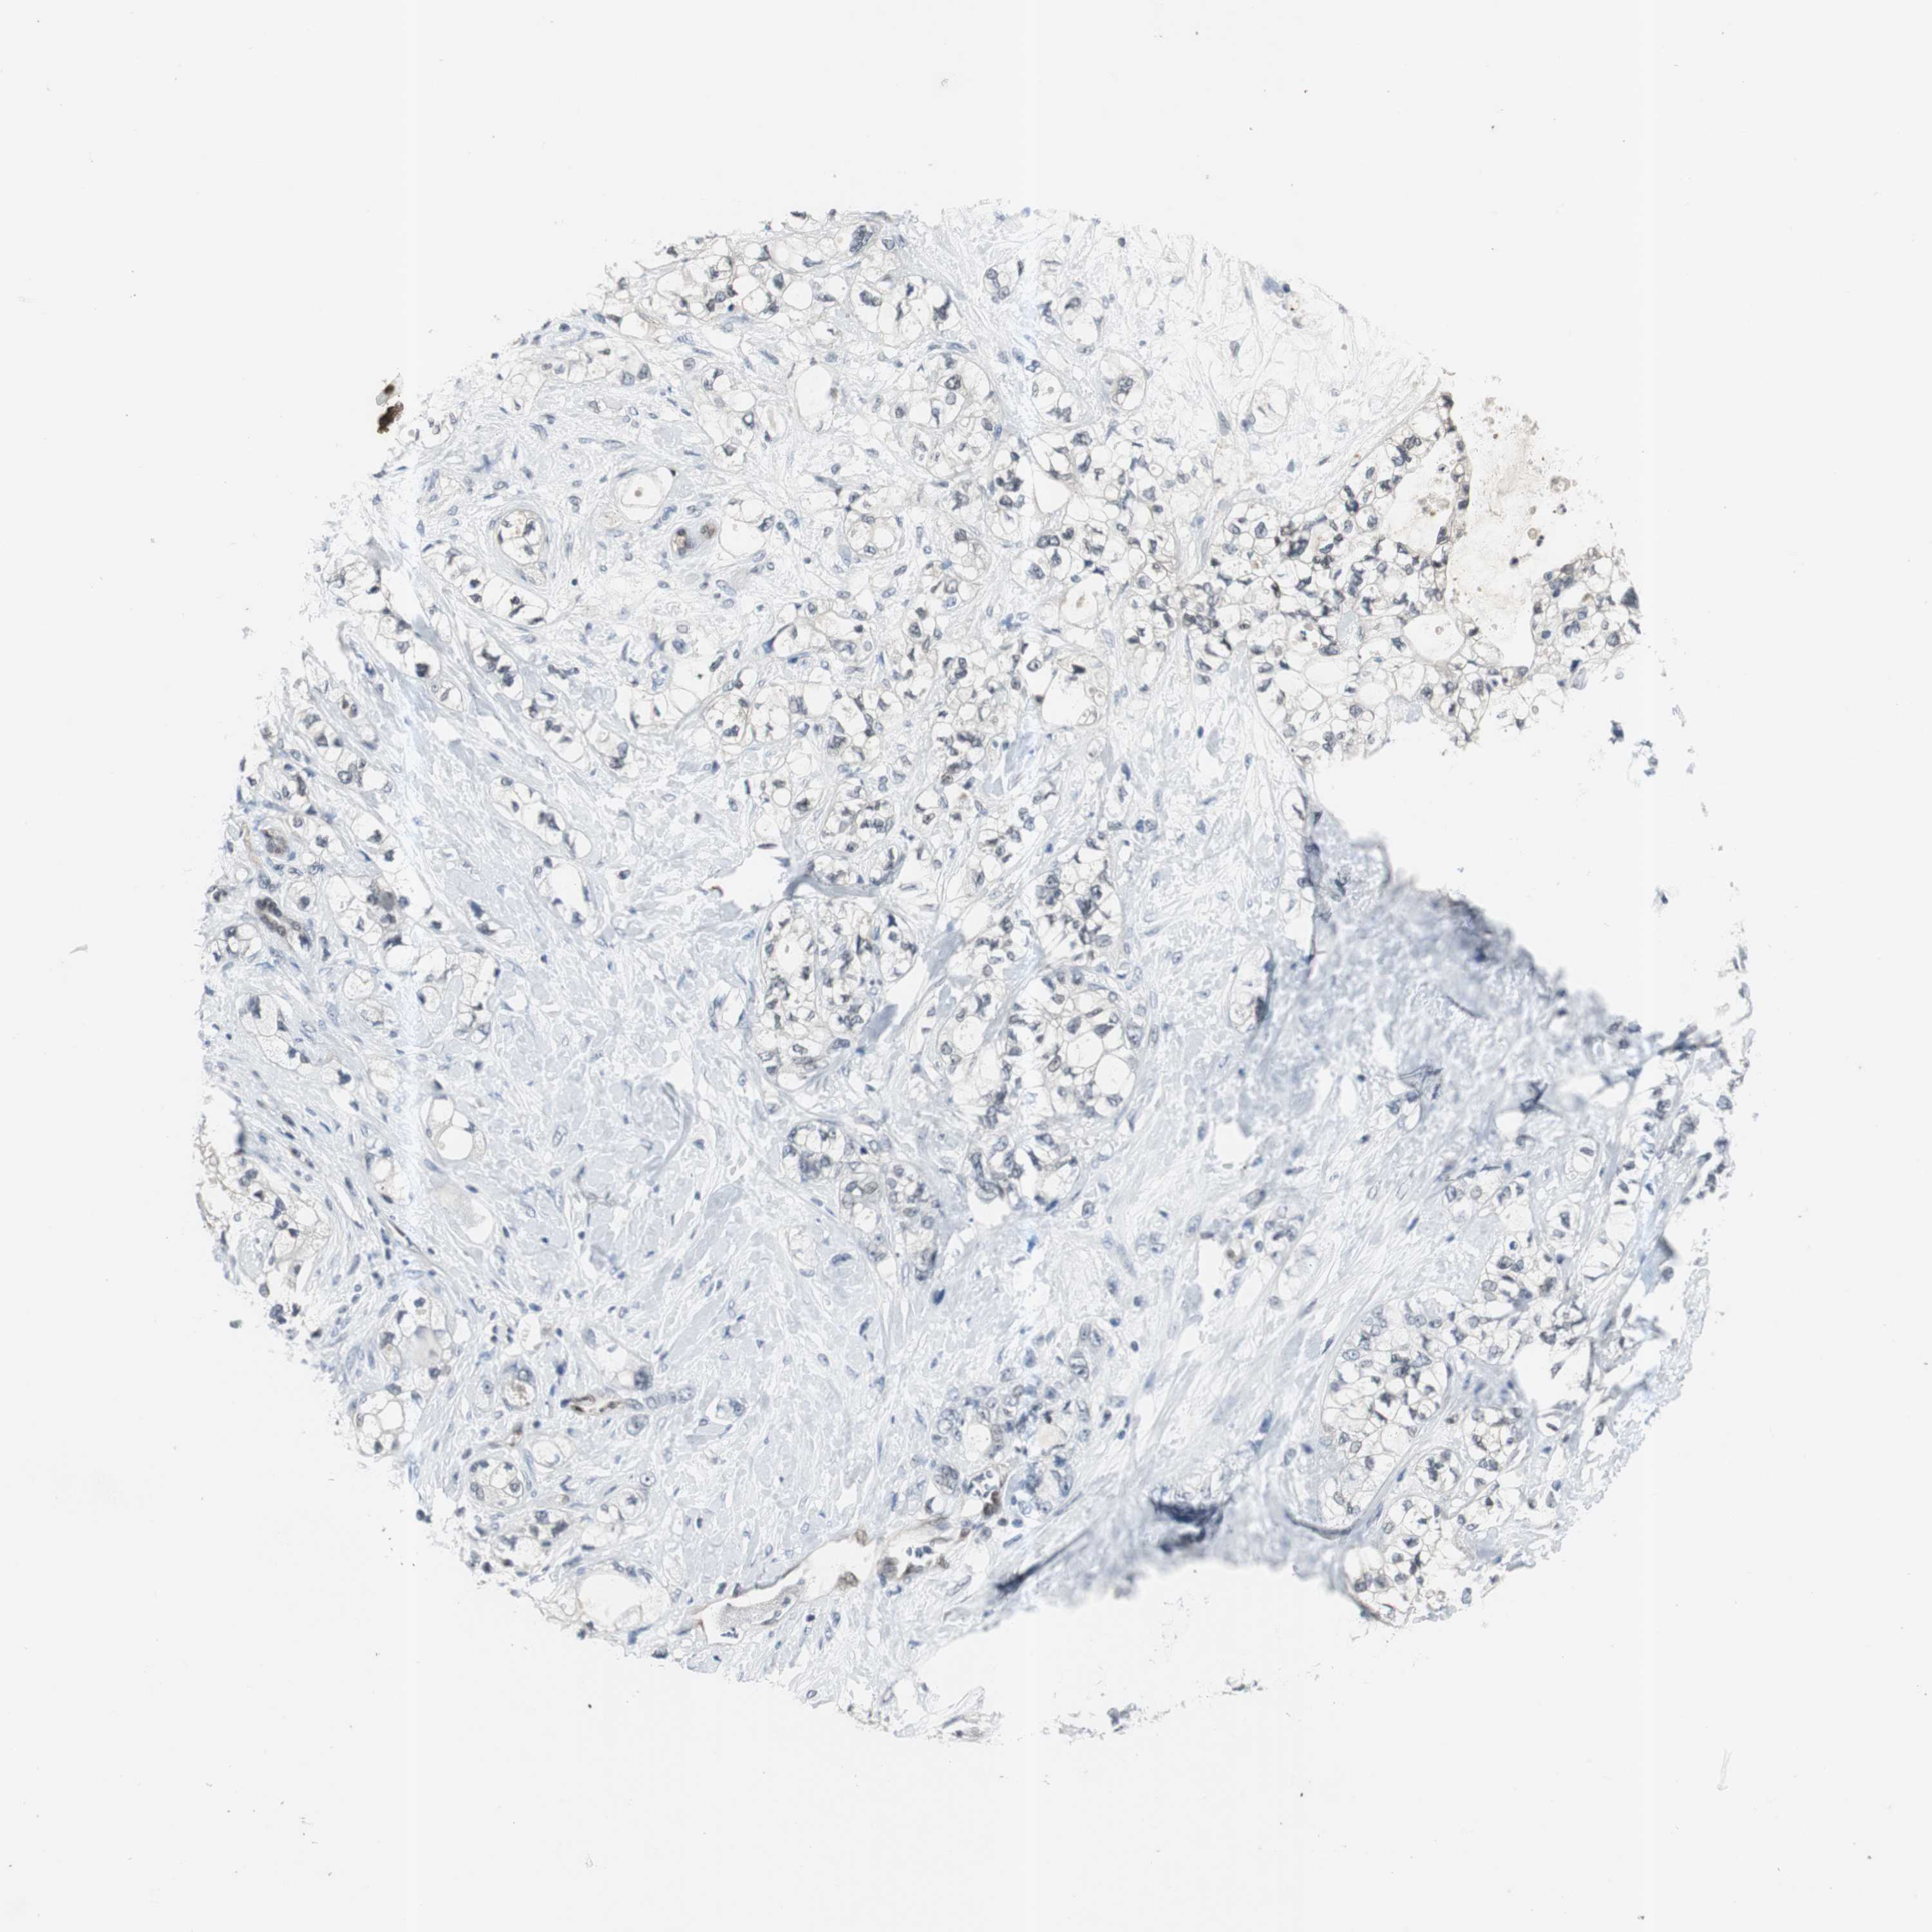

PANCREATIC CANCER - Protein expressioni

A mouse-over function shows sample information and annotation data. Click on an image to view it in a full screen mode. Samples can be filtered based on level of antibody staining by selecting one or several of the following categories: high, medium, low and not detected. The assay and annotation is described here.

Note that samples used for immunohistochemistry by the Human Protein Atlas do not correspond to samples in the TCGA dataset.

Antibody stainingi

Antibody staining in the annotated cell types in the current human tissue is reported as not detected, low, medium, or high, based on conventional immunohistochemistry profiling in selected tissues. This score is based on the combination of the staining intensity and fraction of stained cells.

Each image is clickable and will lead to virtual microscopy that enables deeper exploration of all samples and also displays staining intensity scores, fraction scores and subcellular localization as well as patient and tissue information for each sample.

Antibody CAB005389

Staining

High

Medium

Low

Not detected

Intensity

Strong

Moderate

Weak

Negative

Quantity

>75%

75%-25%

<25%

None

Location

Nuclear

Cytoplasmic/membranous

Cytoplasmic/membranous,nuclear

Adenocarcinoma, NOS

Adenocarcinoma, metastatic, NOS